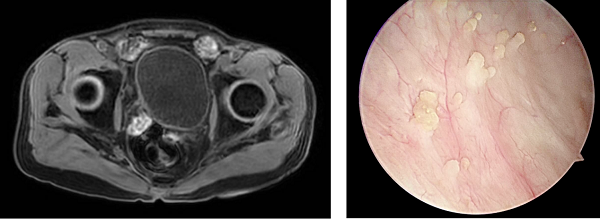

在順利完成3個(gè)周期的規(guī)范聯(lián)合治療后,2026年1月,復(fù)查的影像學(xué)檢查顯示,張先生原膀胱內(nèi)的巨大腫塊已經(jīng)基本消失,受侵犯的輸尿管管壁及周圍組織也得到修復(fù),右腎積水明顯減輕。